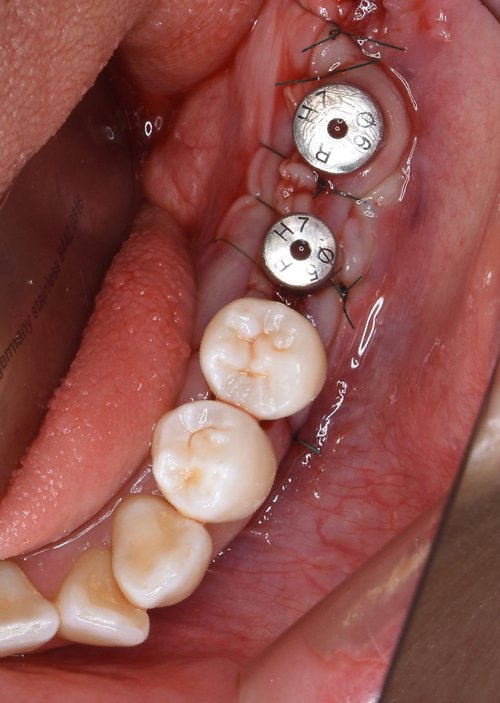

左下の施術終了。

続いて右上の施術開始。

30分程で施術完了。